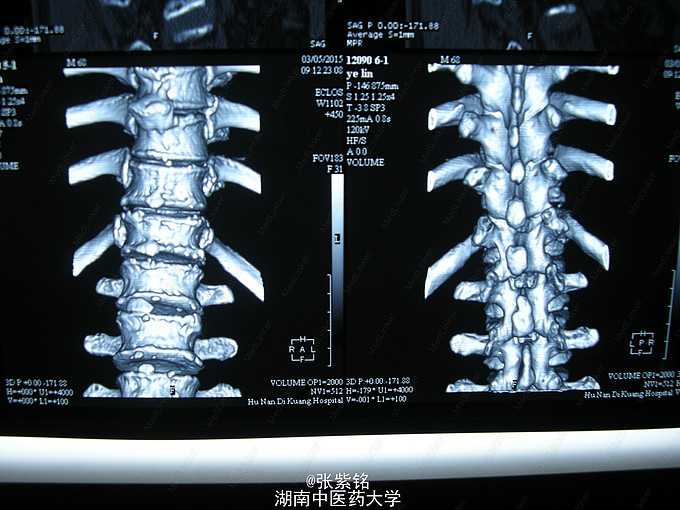

查体见:左额部可见约2cm*2cm皮下血肿,并可见一不规则伤口约2cm,伴活动性出血。脊柱驼背畸形,胸椎后凸,头部前伸体态;颈、腰部旋转活动不能,腰部于L3-5椎体棘突处压痛明显,双下肢肌力、肌张力正常。左肩部关节明显肿胀,可扪及空虚感;局部压痛明显,左Dugas征阳性,左肩关节主动上举,外展,后伸,内收活动受限;被动活动患处疼痛加剧,左侧桡动脉搏动可扪及,皮肤感觉正常,左肘、腕及各指间关节血运感觉活动正常。 X线片示:左肩关节脱位,左肱骨外科颈骨折,左肱骨大结节撕脱性骨折。

1、左肩关节脱位伴大结节撕脱性骨折,2、左肱骨外科颈骨折,3、头部外伤、头面部皮肤裂伤,4、强直性脊柱炎。 1、清创缝合伤口。2、患肢制动,消肿,止痛等对症处理。3、完善相关检查。4、择期行手术治疗及术后对症处理。